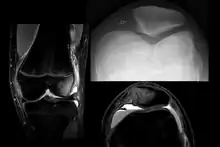

| X-ray showing a patellar dislocation, with the patella out to the side. | |

A patellar dislocation typically occurs when the knee is straight and the lower leg is bent outwards when twisting.[1][2] Occasionally it occurs when the knee is bent and the patella is hit.[1] Commonly associated sports include soccer, gymnastics, and ice hockey.[2] Dislocations nearly always occur away from the midline.[2] Diagnosis is typically based on symptoms and supported by X-rays.[2]

On X-ray, with skyline projections, dislocations are readily diagnosed. In borderline cases of subluxation, the following measurements can be helpful:

- The lateral patellofemoral angle, formed by:[16]

- A line connecting the most anterior points of the medial and lateral facets of the trochlea.

- A tangent to the lateral facet of the patella.

- With the knee in 20° flexed, this angle should normally open laterally.[16]

- The patellofemoral index is the ratio between the thickness of the medial joint space and the lateral joint space (L). With the knee 20° flexed, it should measure 1.6 or less.[16]